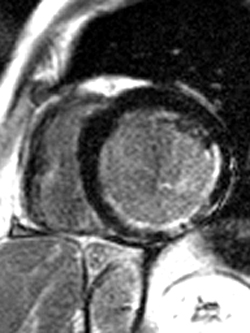

2) This inversion recovery sequence was taken 10 minutes after the administration of IV gadolinium. Which of the following entities does it show?